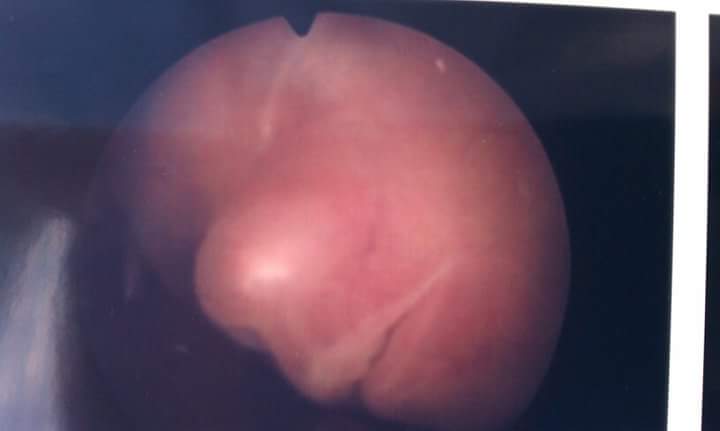

I was considered a rare pregnancy as I used no form of hormone therapy or IVF. We conceived naturally. My pregnancy was extremely difficult. I was diagnosed with very rare conditions like TTTS (Twin-To-Twin Transfusion Syndrome), Cholestasis of Pregnancy (which only 1 in 1,000 pregnant women get), Gestational Diabetes and the list goes on. It seemed at every appointment I went to, I was given bad news, and I seemed to always prepare myself for it.  However, nothing prepared me for the day that I lost baby Zachary Ryan (Baby C).  TTTS had taken one of my babies far too soon and it’s something to this day I still struggle with.  Although I did lose a baby to TTTS, the surgery at 17 weeks saved my other two babies.